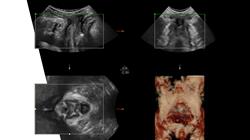

Os avanços nos aparelhos de ultrassom e o maior conhecimento do ser humano nos estágios iniciais da concepção tornaram possível a detecção precoce de anormalidades, o monitoramento da gravidez em diferentes estágios e o diagnóstico preciso de diferentes distúrbios ginecológicos. Assim, os especialistas podem prestar um atendimento de maior qualidade, oferecendo imagens mais realistas e precisas dos fetos.

Nesse sentido, os avanços no ultrassom 3D/4D, no Doppler, no ultrassom transvaginal ou de alta resolução são notáveis. Assim, dados os benefícios e o progresso alcançados por essas técnicas, o especialista é obrigado a se manter atualizado em seu campo. A fim de incentivar esse processo de atualização, a TECH desenvolveu esta Capacitação prática de 120 horas de atividade intensiva em um centro de referência especializado em reprodução humana.

Nesta capacitação de alta qualidade, você aprenderá a realizar de forma adequada e precisa as diversas explorações, como a avaliação do bem-estar fetal, a medição do colo do útero e a identificação de patologias ginecológicas. Também abordaremos a interpretação dos achados ecográficos e a elaboração de relatórios, além de atualizá-lo sobre os avanços tecnológicos e as novas técnicas na área de ecografia obstétrica e ginecológica. Além disso, você aprenderá sobre as últimas ferramentas e equipamentos utilizados na prática ecográfica, assim como as técnicas avançadas de imagem e a aplicação da ecografia tridimensional e em tempo real. E não para por aí! Também discutiremos as perspectivas futuras e as áreas de pesquisa nesse campo em constante evolução. Nossa capacitação em ecografia obstétrica e ginecológica oferece a oportunidade de expandir seus conhecimentos e habilidades nesse campo especializado. Através deste programa, você estará melhor preparado para realizar ecografias obstétricas e ginecológicas de forma precisa, interpretar os resultados e fornecer um atendimento de qualidade aos seus pacientes. Não perca a oportunidade de avançar na sua carreira profissional e fazer a diferença no atendimento obstétrico e ginecológico. Inscreva-se em nossa capacitação em ecografia obstétrica e ginecológica hoje mesmo!